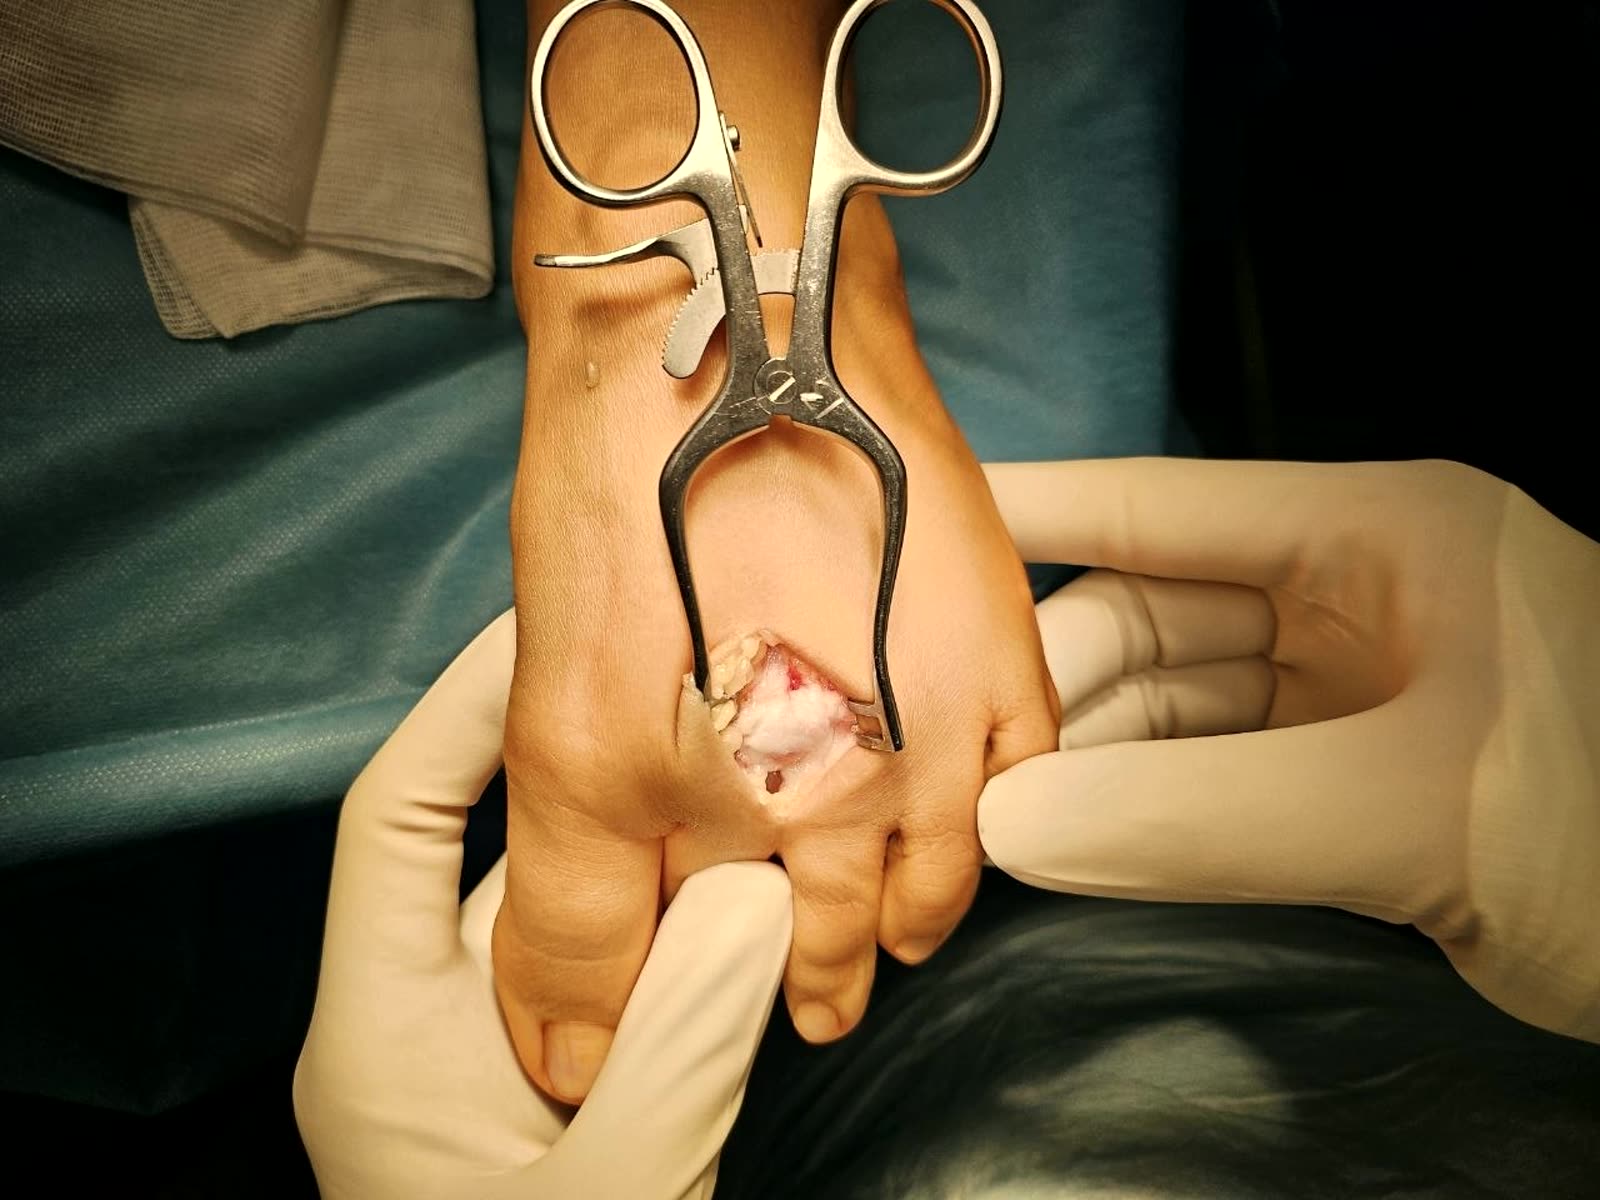

- Показания: переднелатеральный фрагмент (Chaput/Tillaux-Chaput), переднелатеральная колонна

- Разрез между сухожилиями длинного разгибателя пальцев и латеральной лодыжкой

- Переднелатеральный фрагмент присутствует при большинстве переломов с вовлечением суставной поверхности дистального отдела большеберцовой кости [Rammelt et al., JBJS Am, 2022]

Переднемедиальный доступ

- Показания: медиальная колонна, центральная импакция суставной поверхности

- Разрез между сухожилием передней большеберцовой мышцы и медиальной лодыжкой

Принципы выбора доступа

Доступ определяется стратегией репозиции, а не выбором импланта. Основа планирования — аксиальные КТ-срезы на 1 см выше суставной щели голеностопного сустава.

При полных внутрисуставных переломах (43-C) передний доступ предпочтителен в большинстве случаев при адекватном состоянии мягких тканей. Выбор между переднемедиальным и переднелатеральным определяется точкой выхода передней линии перелома на переднюю поверхность большеберцовой кости. Ориентир — передний гребень большеберцовой кости (crista tibiae):

- Линия перелома выходит медиальнее гребня (в сторону медиальной лодыжки) — переднемедиальный доступ. Обеспечивает экспозицию передней и медиальной поверхности плафона, удобен для работы с центральной импакцией. Ограничение: затруднена визуализация латерального желоба и мелких переднелатеральных фрагментов

- Линия перелома выходит латеральнее гребня (в сторону вырезки малоберцовой кости, фрагмент Chaput/Tillaux-Chaput) — переднелатеральный доступ. Обеспечивает визуализацию переднелатеральных фрагментов, синдесмоза и латерального желоба. Более щадящий для мягких тканей. Ограничение: меньшая экспозиция проксимально, часто требует дополнительного доступа

- При центральном выходе линии перелома или при множественных линиях — решение принимается в пользу доступа, обеспечивающего экспозицию наиболее крупного и смещённого фрагмента